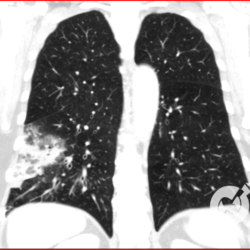

Os agentes etiológicos infecciosos são variados (bactérias, vírus, fungos, parasitas…), mas o que ocorre nos pulmões durante uma infecção por qualquer tipo de agente é a substituição do ar alveolar por secreção (pus, muco, eventualmente sangue ou necrose…) e com isso a manifestação radiográfica vai ser a mesma já que todas estas secreções apresentam a mesma densidade radiográfica: partes moles.

E o nome dado a esta alteração radiográfica que corresponde à substituição do ar alveolar por líquido é a consolidação alveolar.

Uma consolidação alveolar é, por definição, uma opacidade (imagem densa, branquinha) homogênea ou às vezes heterogênea (pela presença de calcificações ou cavidades), de limites mal definidos, exceto quando toca a pleura da parede ou das cissuras pulmonares. É um termo usado tanto em radiografia, como em tomografia computadorizada. Na tomografia, um outro termo é usado: vidro fosco, que é uma opacidade (branquinha mas não tanto como a consolidação), que borra o pulmão mas deixa ver os vasos de permeio (igual bigode de adolescente: dá pra ver todo o fundo).

Nós vamos mostrar aqui um pequeno apanhado de pneumonias de variados agentes, em diversos segmentos e lobos pulmonares, com extensões variadas. O objetivo é identificar o padrão radiológico de consolidação alveolar e não determinar o agente infeccioso, isso vai ser assunto para mais adiante. Aliás já antecipo que é fundamental saber localizar a lesão, porque alguns destes bichos gostam de determinados segmentos, alguns tumores também têm as suas preferências, então localização é fundamental. Se localização não fosse importante, um apartamento na beira do mar sairia o mesmo preço de um apartamento de frente pra BR-101, concordam?